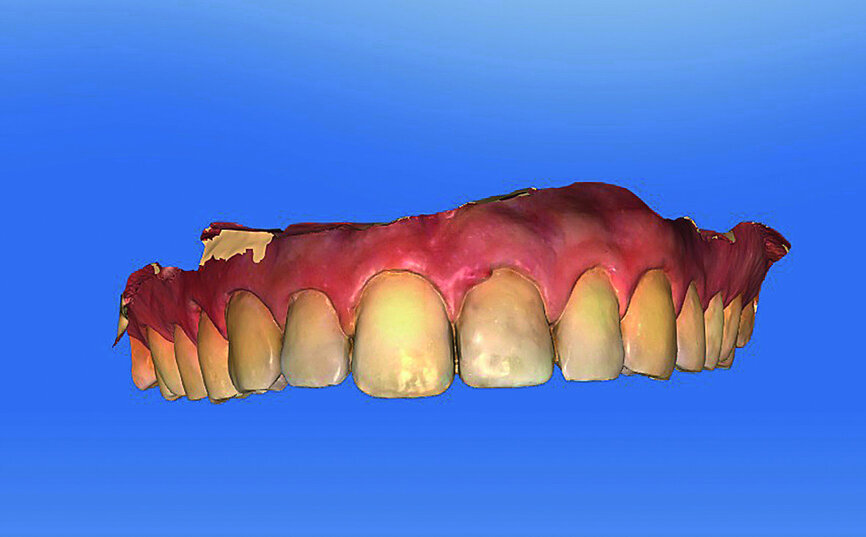

Fig. 1: Single-tooth exposure of tooth #21 after recurrent marginal gingivitis. Owing to the initial diagnosis of extensive resorption, the tooth could not be preserved.

Fig. 2: Initial situation: tooth #21 exhibited marginal redness of the gingiva that bled when probed.

The female patient, born in 1989, came to my practice with problems at tooth #21 caused by a childhood trauma. The gingival margins were reddened and bled when probed. The intraoral radiograph showed posttraumatic resorption of the root, and the tooth could therefore not be preserved (Figs. 1 & 2). The tooth was to be replaced by an implant with an all-ceramic crown immediately after extraction. To plan the procedure, a 3-D radiograph (Orthophos XG 3D, Dentsply Sirona) was taken. It was important to assess the available horizontal and vertical bone and evaluate apical osteolytic processes after the failure of endodontic treatment and in the region of the crestal bone due to progressive dentinal resorption. The integrity of the vestibular lamina was preserved, and there was sufficient apical bone to allow immediate implantation with immediate loading (Fig. 3).